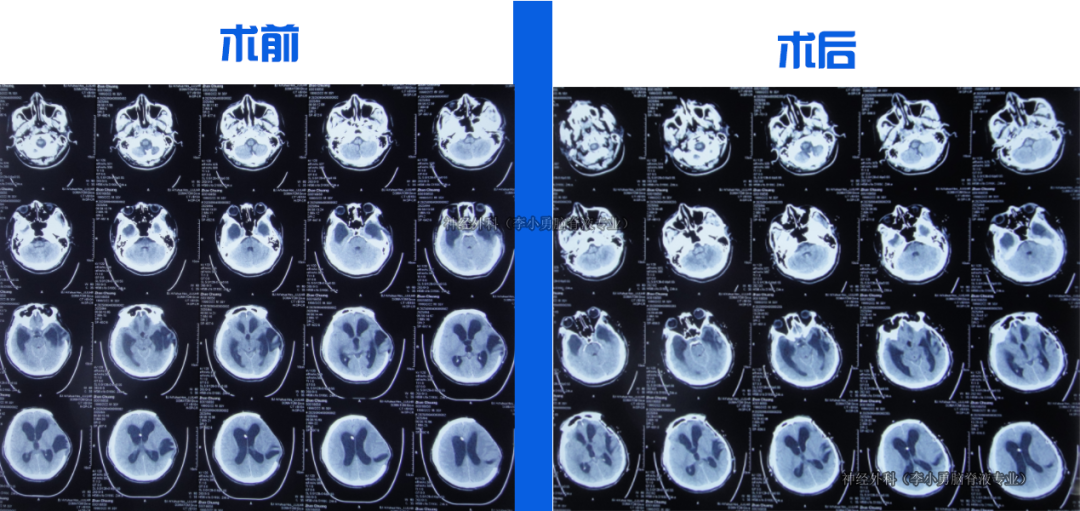

入院当天行脑室外引流术。治疗18天后意识转清,脑脊液由浑浊变清亮。第22天改为脑室腹壁外引流,持续引流、抗感染、控制颅内压力。第36天骨窗开始塌陷,提示颅内压力有效控制。住院1月零23天行颅骨修补术。

经过持续引流和脑脊液净化,患者在治疗2月零6天时能下床走路,3月零2天拔除鼻饲管、走路变稳。在脑脊液化验持续达标后,于住院5月半时行脑室腹腔分流术。治疗近5月余出院时:神志清楚,言语正常,走路基本正常,仅遗留右上肢活动稍差。出院后2月随访,右上肢功能进一步恢复。